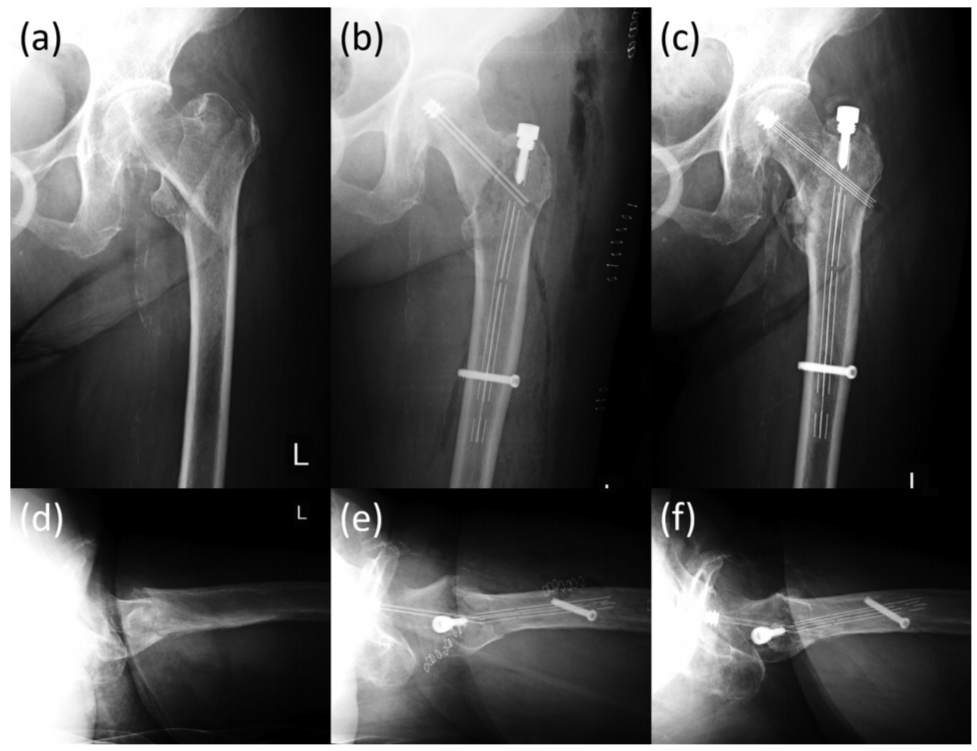

图4 一例89岁股骨粗隆间骨折患者,可见在正位片骨折显示良好,在侧位片上后区由于金属内植物遮挡,骨折部位显示不清。